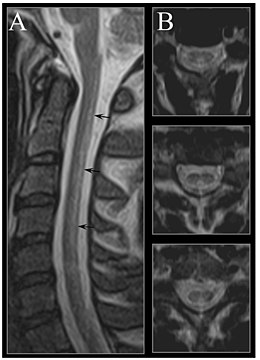

MRI image of the cervical spinal cord in vitamin B12 deficiency showing subacute combined degeneration. (A) The midsagittal T2 weighted image shows linear hyperintensity in the posterior portion of the cervical tract of the spinal cord (black arrows). (B) Axial T2 weighted images reveal the selective involvement of the posterior columns.

MRI of the brain may show periventricular white matter abnormalities. MRI of the spinal cord may show linear hyperintensity in the posterior portion of the cervical tract of the spinal cord, with selective involvement of the posterior columns.